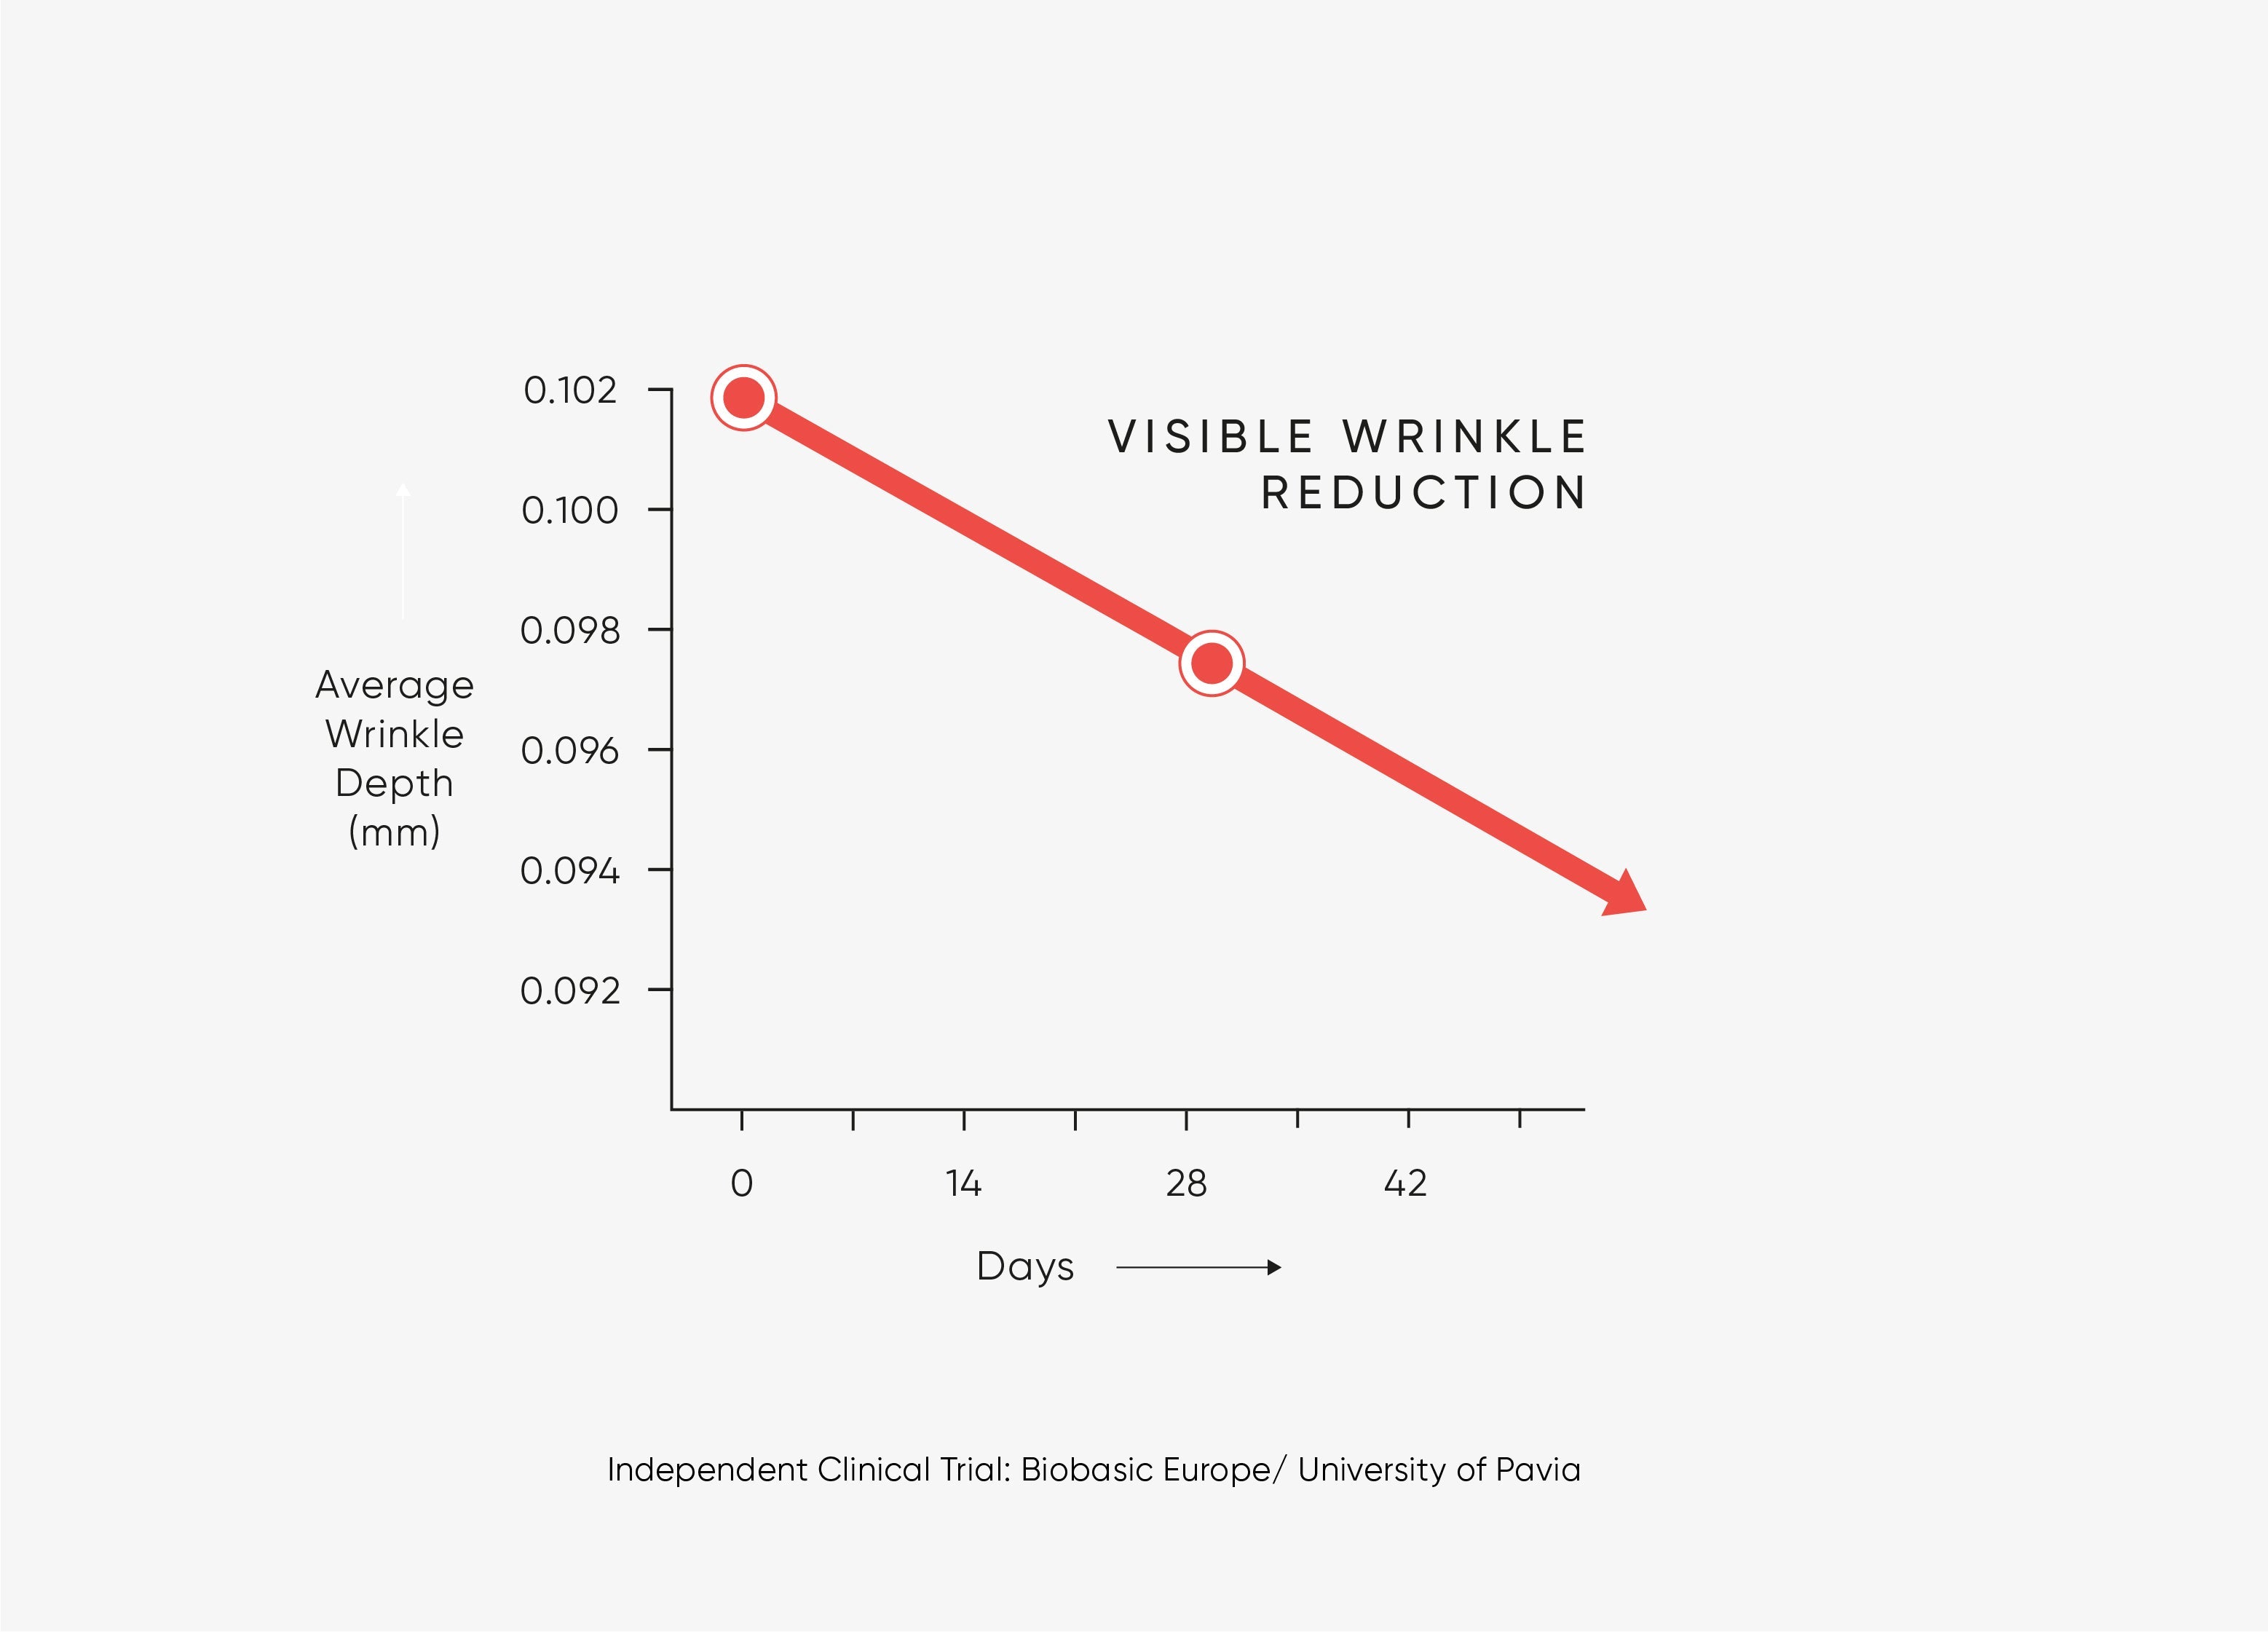

Clinically proven to smooth wrinkles when used in a regime with Hibiscus Serum and Prickly Pear Face Cream.

Clinically proven to smooth wrinkles thanks to neuropeptide Myoxinol™.

USER TRIAL RESULTS AFTER 4 WEEKS*

HYDRATION & MOISTURISATION

100% agree skin looks more hydrated.

95% agree skin feels deeply hydrated.

97% agree skin feels moisturised.

AGE-DEFYING

85% agree skin appears more youthful.

79% agree skin looks years younger.

75% saw a visible reduction in wrinkles.

81% saw a visible reduction in fine lines.

LIFTING & FIRMING

92% agree skin appears lifted.

88% agree skin elasticity improved.

85% agree skin appears plumper.

83% agree skin feels firmer.

HEALTHY & GLOWING

98% agree skin looks healthier.

98% agree skin feels nourished.

90% agree skin looks restored.

89% agree skin appears more glowing.

96% would recommend this product to friends.

*In a 4-week independent consumer trial on 81 participants.